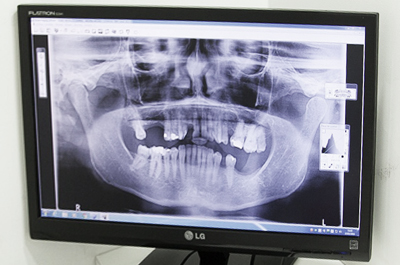

치아를 모두 상실한 경우 필요한 만큼의 임플란트를 식립하여, 치아 전체의 기능을 할수 있도록 합니다.

전체치아의 기능을 회복시켜주기 위해, 치아의 균형을 고려하여 정확하게 식립해야 합니다.

충치, 잇몸질환, 사고 등 다수의 치아가 상실하여 치아가 전혀 없거나

거의 남아 있지 않은 경우, 자연치아가 상실된 상태를 회복하기 위해

임플란트로만 전체를 치료하는 시술이 가능합니다.

이 경우 치아의 기능을 회복하기 위해 잇몸과 뼈상태를 고려하여,

필요한만큼의 임플란트를 식립하게 되고

환자 상태 파악

치아, 뼈는 물론 당뇨, 고혈압 등

건강상태 전반 파악